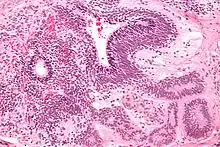

| Micrograph of the primitive neuroepithelium of an immature teratoma. H&E stain. | |

An immature teratoma contains varying compositions of adult and embryonic tissue. The most common embryonic component identified in immature teratomas is the neuroectoderm.[19] Occasionally, tumors may present neuroepithelium that resemble neuroblasts.[19] Tumors may also present embryonic components such as immature cartilage and skeletal muscle of mesodermal origin.[19] Immature teratomas composed of embryonic endodermal derivatives are rare.[19]

Often a mature cystic teratoma is misdiagnosed as its immature counterpart due to the misinterpretation of mature neural tissue as immature.[20] While mature neural cells have nuclei with uniformly dense chromatin and neither exhibit apoptotic or mitotic activity, immature neural cells have nuclei with vesicular chromatin and exhibit both apoptotic and mitotic activity.[20] A recent study has identified the use of Oct-4 as a reliable biomarker for the diagnosis of highly malignant cases of immature teratomas.[21]